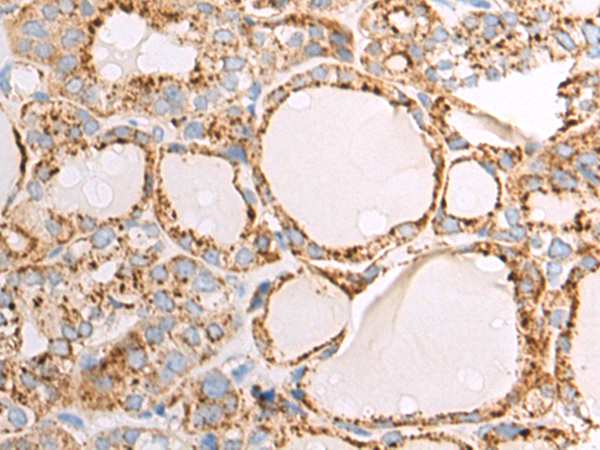

分类: 科研抗体货号: P00274别名: CLEC1; CLEC-1应用: WB,IHC反应种属: Human